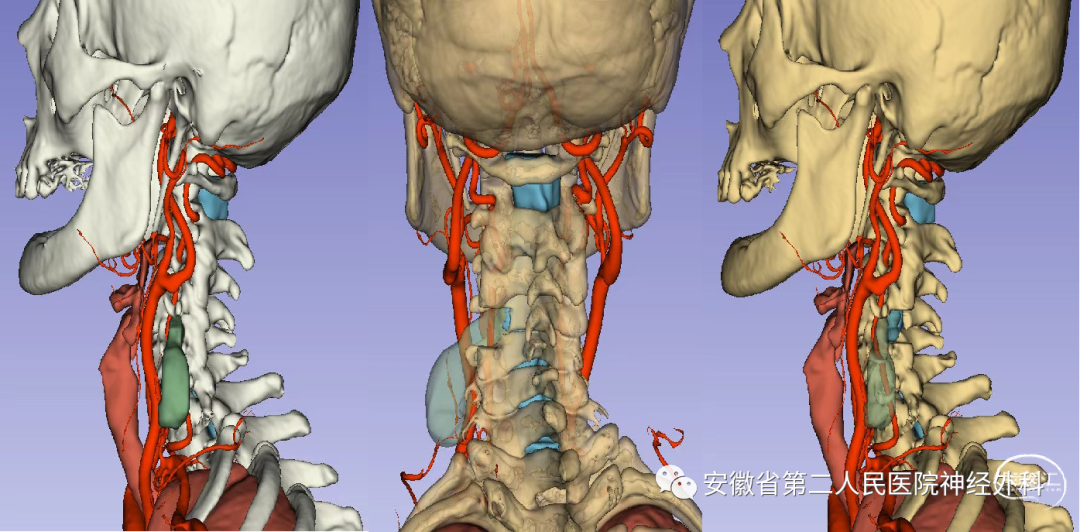

术前3D-Slicer成像

术前评估肿瘤类型并制定手术策略

术前拟定手术方案

患者肿瘤位于高颈段肿瘤,分型为IIb,起源于椎管内神经根并向外生长,手术风险和难度较高,同时合并多阶段颈椎椎间盘突出,术前讨论:考虑同时处理肿瘤和多阶段椎间盘,手术时间长、创伤大、风险高,本次手术拟定先行切除肿瘤+椎板减压,后期视病情行二期颈椎间盘突出手术,手术方案拟在神经电生理监测下经颈前外侧椎间孔入路+备后正中半椎板联合入路切除肿瘤。